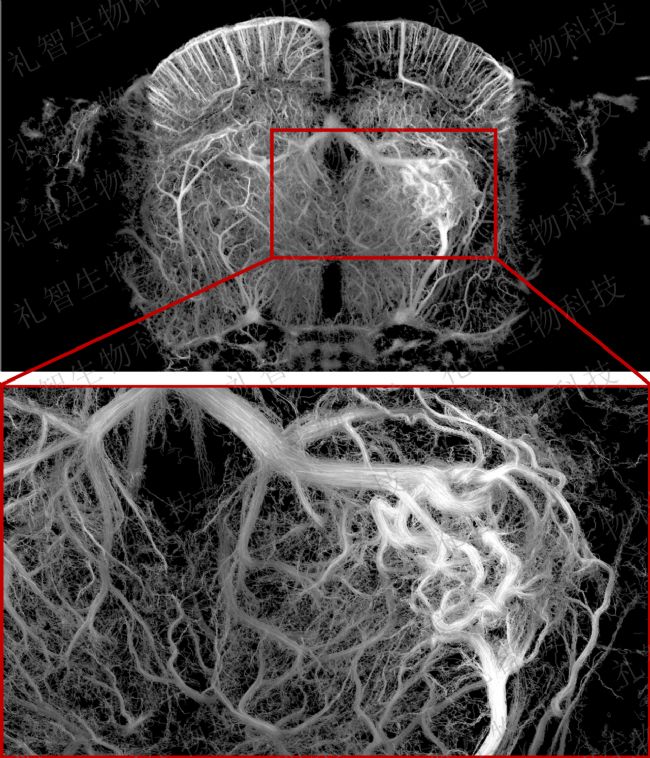

首先干預小鼠大腦皮層下區域建立局部血管畸形模型,然后應用fUS技術中的超高分辨率血流成像(ULM)模塊,實現了對模型動物腦血管形態及血流動力學的動態監測。

圖1.微血管結構重建圖像:清晰呈現了血管畸形的空間構型及微血管網絡特征。圖來源:禮智生物科技